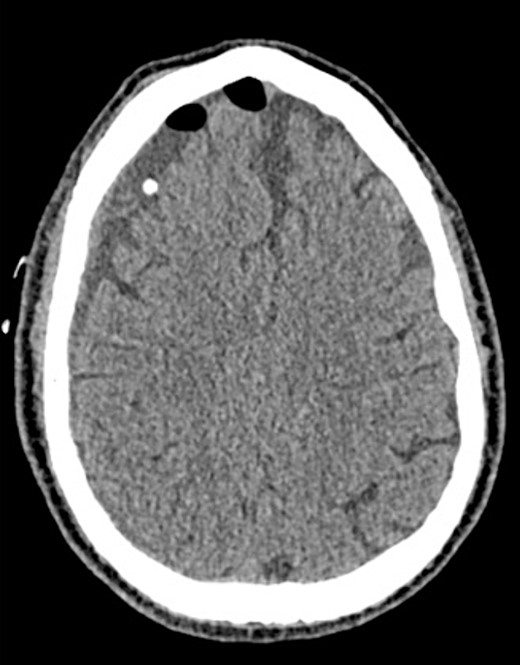

An 81-year-old male with a history of acute subdural hematoma, previously managed non-surgically, presented with worsened confusion and cognitive dysfunction. Repeat CT demonstrated expansion of right-sided subdural collection, consistent with cSDH (Fig. 4).

After the head was positioned in a supine neutral position on a horseshoe head holder, the AR system was used to overlay the hematoma and other relevant anatomy onto the patient’s head. Midline locations, vasculature and the blood collection were appreciated via AR overlay prior to marking an incision (Fig. 5). The AR overlay was then used to plan two separate linear incisions for two right-sided burr holes—one frontal and one parietal over the largest components of the hematoma as visualized with AR. A perforator drill was used to create the two burr holes which were widened with a burr and rongeurs. Beneath the dura, a hematoma was identified and its thick membrane layer was coagulated with bipolar cautery. The surgical sites were irrigated with saline to evacuate chronic blood. A ventriculostomy catheter was then placed into the subdural space at the frontal burr hole and tunneled lateral to the incisions. The burr holes were covered with titanium covers. There were no intraoperative complications, and the tolerated procedure well with improved cognitive function several days after surgery. Post-operative CT demonstrated significant interval decrease in hematoma volume and reduction in midline shift (Fig. 6).